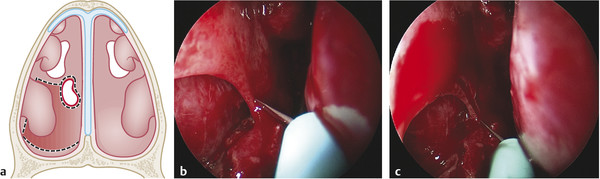

Start measuring the size of the NSP to set the extension of the flap. To improve exposure, it can be useful to outfracture the inferior turbinate (Fig. 17‑2a).

Incisions (Fig. 17‑2b):

Two parallel incisions are made through the floor of the nose; the first should be located at least 5 mm anterior to the anterior border of the septal perforation, and the second incision at least 5 mm posterior to the posterior border of the perforation.

Anterior incision usually starts in the inferior meatus, at the level of the piriform aperture and it is extended medially along the nasal floor until the premaxilla.

Posterior incision runs parallel to the anterior incision but begins at the junction between the soft and hard palate and, if needed, can be extended laterally to the posterior insertion of the inferior turbinate.

Lateral incision connects the two previous cuts (anterior and posterior) along the inferior meatus. For large perforations, the extended version of this flap including the mucosa of the inferior turbinate can be achieved by placing the lateral incision higher in the lateral wall. 4 , 5